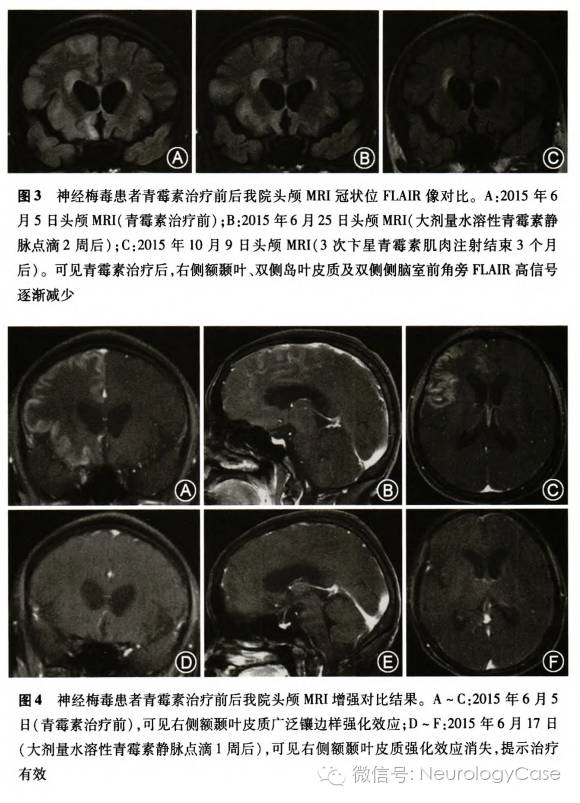

患者女性,50岁。2015年5月31日于立位时突发左侧肢体强直及强迫左侧头位,至当地医院急诊,给予地西泮10mg静脉推注,左侧肢体强直转为持续肌阵挛。6月2日左下肢瘫痪,左上肢肌阵挛及强迫左侧头位仍持续存在,6月4日至我科住院。病程中无意识丧失,无发热。20年前从事皮鞋加工半年,近1年反应迟钝、记忆力减退。入院体检:意识清楚,强迫左侧头位,左上肢持续肌阵挛,表现为左手及左肘关节1次/1-2s的节律性抽动,左上肢肌力II级,左下肢肌力I级,右侧肢体肌力IV级,双上肢肌张力高,双下肢肌张力正常,四肢腱反射亢进,左侧偏身针刺觉减退,双侧病理征(+)。颈强直,克尼格征(-),布鲁津斯基征(-)。辅助检查:腰椎穿刺脑脊液压力145mmH2O(1mmH2O=0.0098kPa),白细胞计数8×10^6/L,蛋白定量0.60g/L,葡萄糖和氯化物水平正常;革兰阴性双球菌染色、抗酸染色、墨汁染色均阴性;病毒筛查、自身免疫性脑炎相关抗体检查均阴性。血清梅毒螺旋体明胶颗粒凝集(TPPA)试验阳性,甲苯胺红不加热血清(TRUST)试验阳性(1:4)。脑电图示:广泛持续性周期性三相尖波(图1A)。头颅MRI示右侧额颞叶、双侧岛叶皮质及右侧丘脑可见多发长T2信号及FLAIR高信号,双侧侧脑室前角旁可见片状长T2信号及FLAIR高信号(图2A,3A);右侧额颞叶皮质广泛镶边样强化效应(图4A-C)。头颅MRA正常。入院当日考虑病毒性脑炎及克雅病不除外,给予更昔洛韦静脉点滴,同时考虑肌阵挛为肌阵挛性癫痫持续状态可能大,给予抗癫痫治疗,但肌阵挛仍持续存在。入院次日血清TPPA试验及TRUST试验均阳性。追问个人史补充如下:患者及其丈夫均有婚外性接触史,进一步查脑脊液TPPA试验阳性,TRUST试验阳性(1:1),同时送检脑脊液14-3-3蛋白(1周后回报阳性)。患者神经梅毒诊断明确,停用更昔洛韦,改水溶性青霉素2400万IU/d静脉点滴。治疗4d后患者左侧肢体肌力IV级,右侧肢体肌力V级,左上肢肌阵挛、强迫左侧头位及颈强直均消失,左侧肢体针刺觉正常,1周后脑电图三相波消失,表现为间断性周期性尖波、慢波(图1B),头颅MRI强化效应消失(图4D-F)。2周后脑脊液TRUST试验转为阴性,TPPA试验仍为阳性,白细胞计数5×10^6/L,蛋白0.55g/L,头颅MRI平扫示颅内病灶减小(图2B,3B)。患者生活能自理并出院。门诊继续予卞星青霉素240万IU每周1次肌肉注射,共3次,复查脑电图未见癫痫样放电及慢波,但基本节律稍差(图1C)。2015年10月初患者因左侧颞顶部疼痛及左侧偏身麻木感再次住我科,复查血清TRUST试验阳性(1:2),TPPA试验阳性;脑脊液白细胞计数2×10^6/L,蛋白0.41g/L,TRUST试验阴性,TPPA试验阳性;脑电图恢复正常(图lD),头颅MRI平扫示颅内病灶继续减小(图2C,3C)。再次予水溶性青霉素2400万IU/d静脉点滴1周,继之予卞星青霉素240万IU每周1次肌肉注射,共3次,患者头痛明显好转,左侧偏身麻木感消失,仍反应及言语慢。

本例患者血清、脑脊液的TRUST试验及TPPA试验均阳性,结合病史、影像学检查及青霉素治疗有效等,诊断神经梅毒;结合病程较短、皮质强化效应明显、无脑萎缩、青霉素治疗后颅内病灶明显减小等特点,分型属脑膜血管型。下面对其特殊的临床表现、脑电图改变及鉴别诊断分别讨论。

三相波最初发现于肝性脑病的患者,1955年被正式命名,后来也见于其他代谢性脑病、中毒、缺氧性脑病、电解质紊乱和结构性损伤的患者,提示存在广泛性脑功能损害神经梅毒的脑电图常表现为单一节律的θ波或δ波暴发,背景活动慢化,局限性的慢波或癫痫波,国内外罕有表现为三相波的报道。姜坤等曾报道1例表现为记忆力减退伴癫痫发作、精神行为异常的神经梅毒患者,脑电图可见右侧大脑半球周期性三相波,但患者表现为四肢抽搐伴意识障碍,不属于非癫痫性肌阵挛。我们报道的病例在肌阵挛发作期间脑电图呈广泛性持续性周期性三相波,头颅MRI增强可见右侧额颞叶皮质广泛强化效应,青霉素治疗1周后强化效应消失,肌阵挛亦消失,三相波转为周期性尖波、慢波,提示神经梅毒患者肌阵挛和三相波的出现均与皮质炎性反应有关。此外,三相波多见于有意识障碍者,罕见发生于意识清楚的患者。毛善英等曾报道1例帕金森病伴肌阵挛患者,脑电图呈三相波改变,美多巴治疗后肌阵挛发作得到控制,三相波消失,与本例神经梅毒患者类似,均意识清楚。这表明三相波虽提示脑功能广泛受损,但患者不一定出现意识障碍